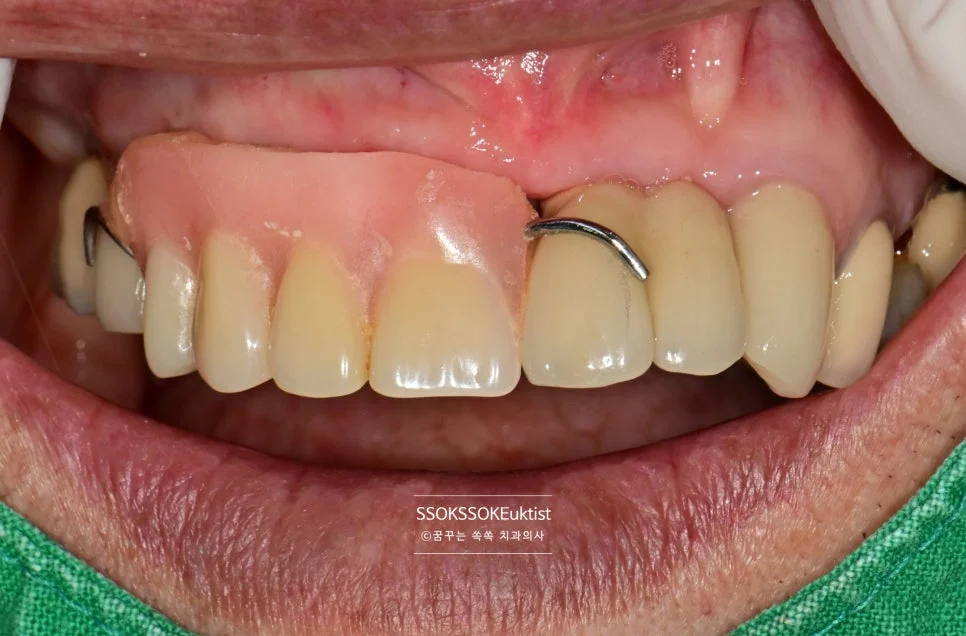

Step 4. 임시 틀니(Flipper) 장착

임시 틀니(Flipper) 장착 모습

발치 후 임플란트가 유착될 때까지는 2~4개월 정도 기다려야 하는데, 앞니의 경우 이가 없으면 너무 보기가 좋지 않죠. 임시로 사용할 수 있는 틀니를 제작해 드려 불편함을 최소화합니다. (Flipper, 임시틀니)